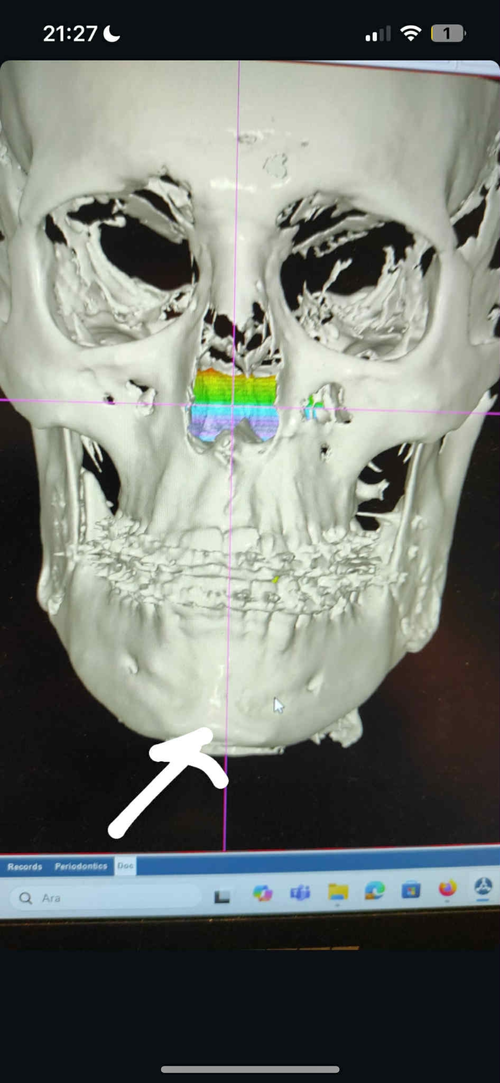

He rotated my proximal segment assymetrical.

If you look at my before and after you will see how my left side after the surgery tilts more downwards, while my right are more upwards.

This was his completely brilliant idea of fixing the assymetry.

The genioglossus are attached to the mandible, rotating the proximal segment assymetrical=assymetrical tongue.

He rotated my proximal segment assymetrical.

If you look at my before and after you will see how my left side after the surgery tilts more downwards, while my right are more upwards.

This was his completely brilliant idea of fixing the assymetry.

The genioglossus are attached to the mandible, rotating the proximal segment assymetrical=assymetrical tongue.